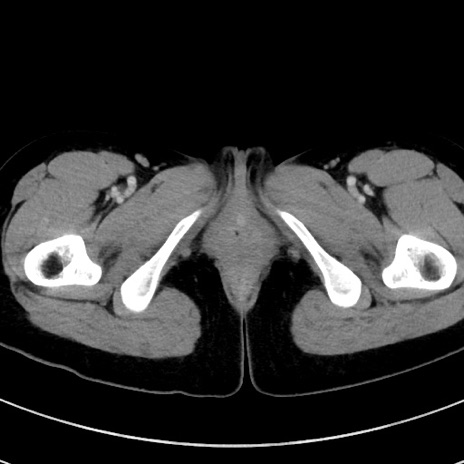

症例17(横断像)

【症例】20歳代女性

【主訴】嘔吐、下腹部痛

【現病歴】昨日夕食後に嘔吐し下腹部痛が出現。本日になっても嘔吐持続し改善しないため来院。

【身体所見】意識清明、BT 37.2℃、BP 108/67mmHg、腹部:平坦、やや硬、下腹部正中から右にかけて圧痛あり、反跳痛軽度あり、tapping pain(+)。

【データ】WBC 13600、CRP 14.94